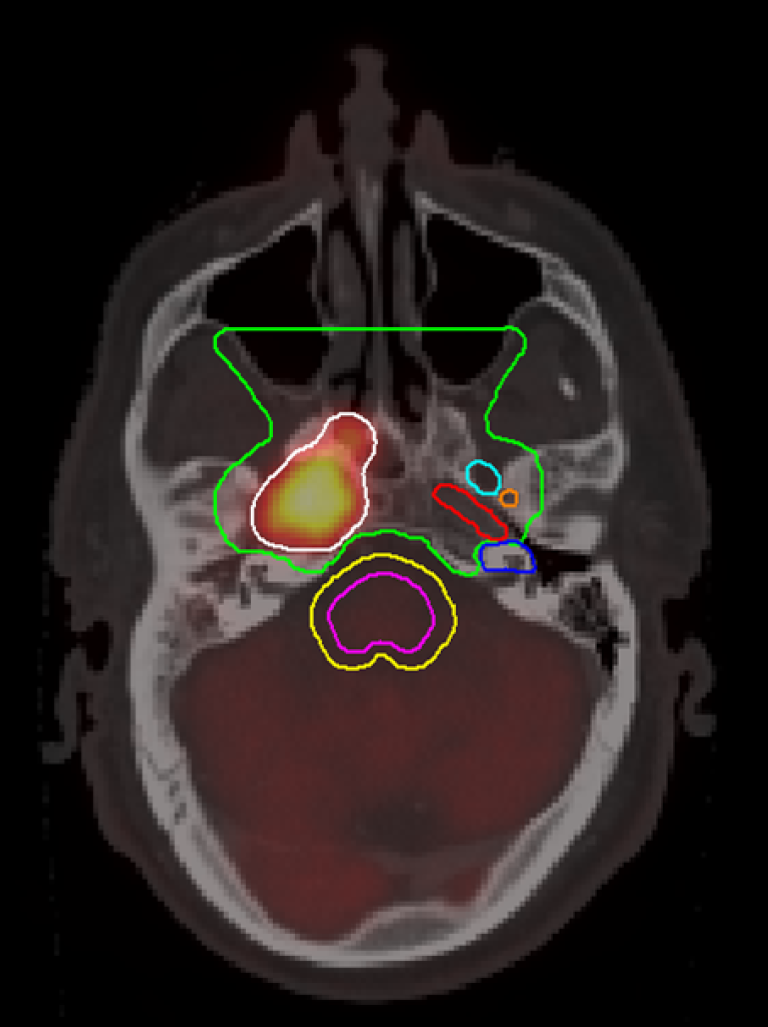

Figur 15.4: CTV3 nasofarynks (lys grønn) i skallebasis nivå. For øvrig inntegnet foramen ovale (lys blå), foramen spinosum (orange), carotis kanal (rød), cochlea (mørk blå), hjernestamme (fiolett), PRV hjernestamme (gul). Merk gjennomvekst av primærtumor gjennom carotis kanal på høyre side (hvit). Laget av handlingsprogramgruppen.